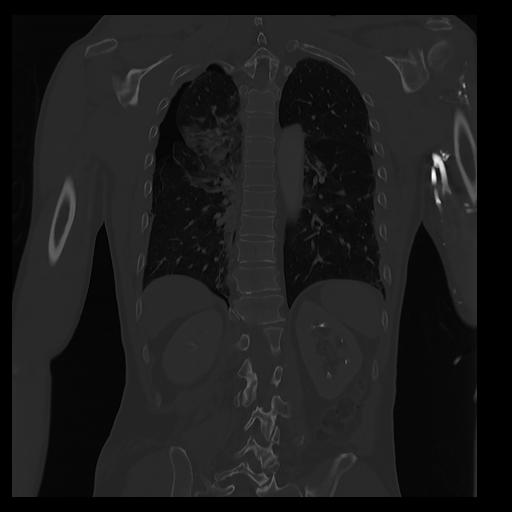

32 PULMON,CE,Coronal,3.000,PULMON,Coronal,